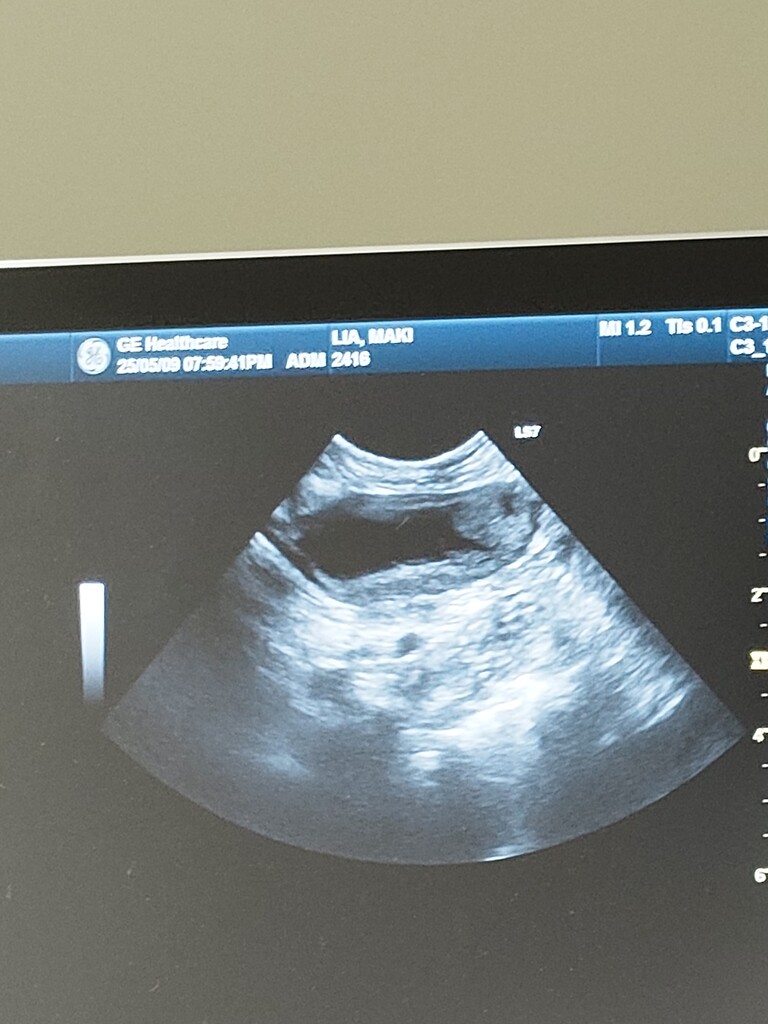

なので整形専門医のいる病院へ

レントゲンでは異常は見つからず

触診でも、いつもスーンな表情だったらしく

原因わからず。